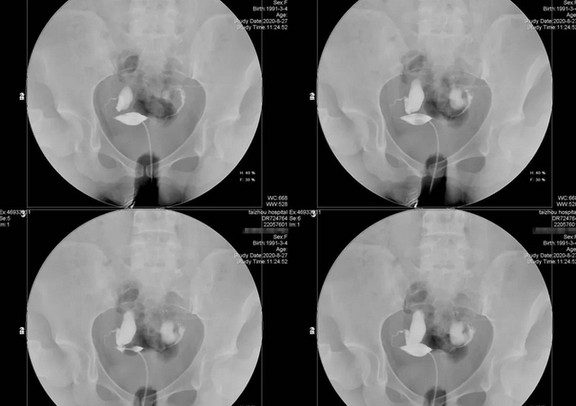

3、输卵管的通畅性

输卵管是生育的桥梁,其通畅无阻且功能正常,女性才能顺利怀孕。有过流产经历、宫腔操作,得过盆腔炎等炎症的女性,输卵管很容易出现堵塞、粘连、积水、通而不畅等问题。

一般在月经干净后3-7天做输卵管造影,查看输卵管的健康状况,以及病灶的具体位置。